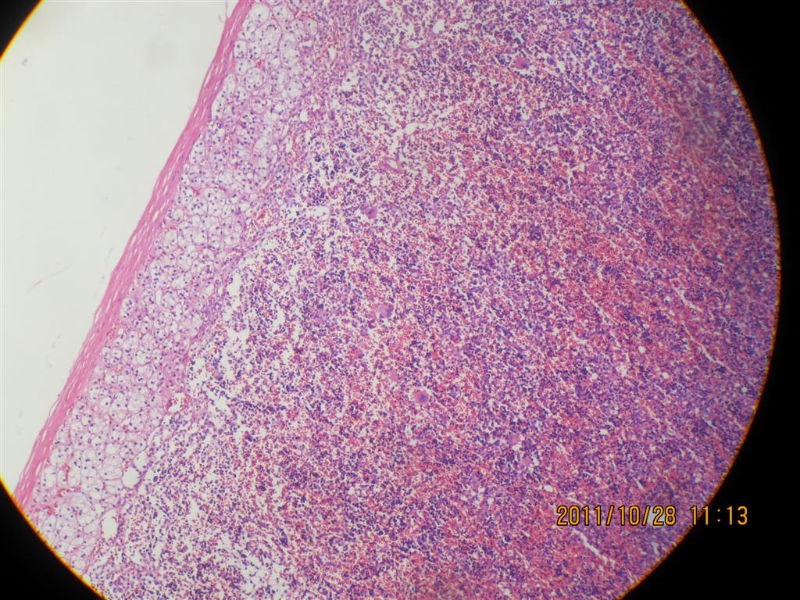

髓脂肪瘤